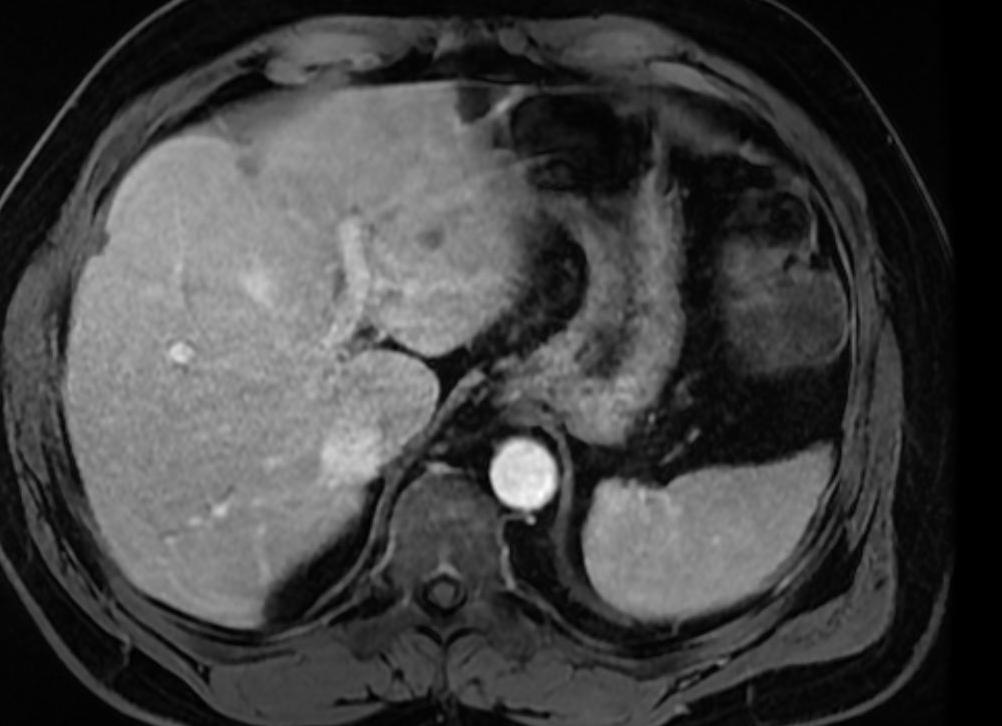

16-03-2014, 14:27 16 778 строение печени человека Магниторезонансная томография внутренних органов брюшной полости позволяет определить изменения в форме, плотности и функционировании с помощью безвредного для человека магнитного воздействия на ткани организма. Индукция постоянного магнитного поля, генерируемого постоянными магнитами или электромагнитными катушками, может достигать довольно больших величин – до 3 и более Тл (Тесла). Вредного воздействия магнитного постоянного и переменного полей на клетки организма не обнаружено, поэтому, считается, что исследования МРТ не влияют ни на нормальное состояние пациента ни на динамику развития болезни.МРТ применяется исключительно с целью диагностики и наблюдения за динамикой лечебного процесса, с целью выработки определенной тактики лечения и принятия решения об оперативном вмешательстве. Очень эффективно применение томографов в онкологии, особенно МРТ с контрастом печени.Печень – один из важнейших органов человека. Кроме участия в процессах пищеварения и кровообращения она выполняет очень ответственную функцию очистки организма от агрессивных веществ, токсинов, аллергенов, избыточных гормонов, продуктов распада алкоголя. Можно сказать, что печень постоянно находится на переднем крае сражения с патогенными веществами, поэтому и страдает в первую очередь.Заболевания печени очень опасны для общего состояния организма. При тяжелых поражениях и нарушении функциональности печени неизбежно страдают другие органы, некоторые болезни на современном этапе развития медицины неизлечимы, но многие можно победить, если своевременно обнаружить и начать лечение.В общем случае печень исследуется по методу магниторезонансной панкреатохолангиографии, показывающей внешние и внутренние желчные протоки и панкреатические протоки. С помощью этой методики легко обнаруживаются различного рода новообразования или подтверждается их отсутствие. Параллельно с ним используется и другой метод – холецистохолангиография с помощью МРТ. Он исследует состояние желчного пузыря и протоков.Но для более точного определения наличия новообразований применяется МРТ печени с контрастированием. Усиление контраста изображения позволяет выделить зоны опухолей с определением их точных границ, размеров и наличия метастазов. Отличие процессов обмена в здоровых и пораженных раком тканях определяется отличием структуры клеток, которая проявляется в различных реакциях на магниторезонансное возбуждение.

подготовка к проведению МРТ печени с контрастом Информативность МРТ зависит от определения различия в структуре ткани. Возбуждение атомов водорода магнитным полем переменной частоты может изменяться при наличии в клетках некоторых веществ, являющихся естественными активаторами атомов, и усиливают интенсивность отклика именно атомов, содержащихся в клетках организма. Этим действием они отличаются от веществ, использующихся для контрастирования при рентгенографии.Эти вещества, например, соли бария, при облучении рентгеновскими лучами видны хорошо сами по себе, и определение пораженных участков осуществляется путем осмотра прилегающих к контрастному фону областей.Иной механизм действия усилителей контраста при МРТ. Они проникают вместе с кровотоком в мельчайшие капилляры и активируют все клетки, как больные, так и здоровые. Их реакция отклика на магнитное поле переменной частоты различна, поэтому и изображение на дисплее томографа будет сильно отличаться. МРТ с контрастом печени, как и иных органов, очень сильно зависит от интенсивности кровообращения в исследуемой области.Печень отличается высокой насыщенностью кровеносными сосудами, поэтому и МРТ печени с контрастом показывает очень четкую картину изменений. С его помощью можно выявлять;

МРТ печени с контрастированием

Контраст в ходе проведения МРТ оказывает усиливающий эффект для диагностики. Контраст вводится пациенту внутривенно, после чего, спустя некоторое время, активизируются все клетки организма до мельчайших капилляров. Примечательно, что МРТ печени без контрастов показывает лишь больные клетки. Стоит отметить, что в ходе проведения МРТ печени с контрастами, качество изображения результатов также зависит от функциональности кровеносной системы пациента в той области, которая подлежит исследованию. Однако при диагностике печенки, картина, как правило, четкая, по причине обилия кровеносных сосудов, расположенных в полости органа.

Что показывает МРТ печени с контрастом:

- плотность и однородность деформированных тканей при патологиях;

- характер опухоли;

- форму и размер органа;

- наличие метастаз и их точное месторасположение;

- поражения механического характера (следствие травм и операций);

- места сосудистых повреждений и закупорок;

- области поражения токсинами

Важно знать, что МРТ печени с контрастом показывает высокую результативность, при условии интенсивного кровоснабжения. Таким образом, чем выше насыщенность кровотока, тем ярче визуализирован контраст.

Как делают МРТ печени с контрастом

Контраст – это жидкий препарат с особым составом, который позволяет детально рассмотреть на снимке те участки печени, которые без контрастирования увидеть невозможно.

Контрастирование показано тогда, когда есть необходимость пронаблюдать за течением болезни в динамике, диагностировать опухоли, которые на снимке сливаются с паренхимой.

Для печени характерна высокая насыщенность кровеносными сосудами, куда в первую очередь поступает контрастное вещество. Оно проникает в самые мелкие капилляры, вступая во взаимодействие как с больными, так и со здоровыми клетками. На выходе получаются очень четкие снимки срезов, позволяющие определить:

- Закупорку или патологическое сужение вен, артерий и протоков;

- Опухоли и метастазы;

- Травматические поражения тканей;

- Отклонения от нормы показателей тканевой плотности и однородности.